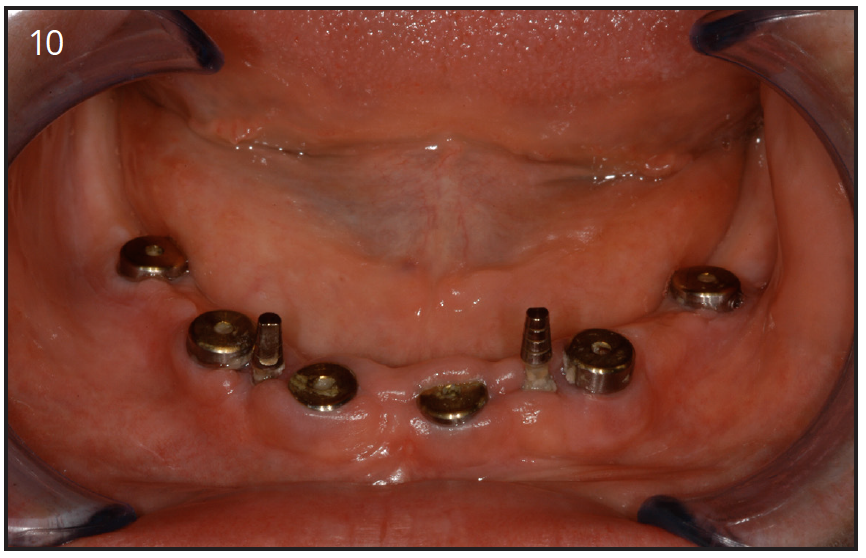

Mini-implants were introduced in dentistry as a temporary implant. These were placed to support a denture, or temporary prosthesis during the healing time following implant surgery.21,22 (Figure 10) Several manufacturers are now produce mini-implants for permanent restoration of missing teeth. The cost of mini-implants is approximately ¼ of the cost of a regular implant; however, the studies show a success rate of 60-70% during 5 years in function.

Figure 10 – Six implants placed in the lower arch with 2 mini-implants to help keep denture stable

Figure 10